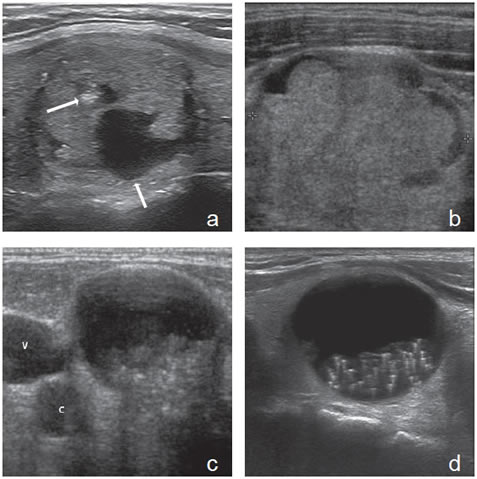

Las microcalcificaciones aparecen en la ecografía como focos ecogénicos puntiformes, sin sombra acústica y sin artefacto por reverberación, en el espesor del tejido sólido (Figura 8a). Desde el punto de vista histológico corresponden a conglomerados de cuerpos de psammoma, que son esférulas microscópicas laminarmente calcificadas. Se originan a partir de células necróticas, a menudo en las puntas de las papilas, que forman el nido sobre el cual se depositan las láminas de calcio. Se encuentran principalmente en carcinomas papilares (29% a 59%), pero pueden estar presentes en carcinomas medulares y anaplásticos11,16.

Las macrocalcificaciones aparecen como placas ecogénicas fragmentadas, o depósitos granulares amorfos que determinan sombra acústica hacia los planos profundos (Figura 8b). Patológicamente corresponden a calcificaciones distróficas secundarias a necrosis y fibrosis. La distribución puede ser central o periférica y ocurrir tanto en nódulos malignos como nódulos benignos de larga data. En el cáncer papilar pueden coexistir microcalcificaciones con calcificaciones gruesas, que se depositan en áreas de fibrosis y degeneración; las calcificaciones granulares centrales son el tipo más frecuente en el cáncer medular.

De todos los signos ecográficos asociados a malignidad, las microcalcificaciones es el más específico (85-95%). La presencia de microcalcificaciones en un nódulo predominantemente sólido aumenta el riesgo de cáncer en tres veces y la presencia de calcificaciones gruesas aumenta el riesgo de cáncer en dos veces. El valor predictivo de las microcalcificaciones varía entre 42% a 94% y la sensibilidad entre 26% a 59%5.

Según la distribución de los vasos sanguíneos, los nódulos tiroideos se describen como hipovasculares (Figura 11), isovasculares (los menos frecuentes) e hipervasculares. En los hipervascularizados, se describen dos patrones. Un patrón de vascularización periférica (Figura 12) tiende a ser una característica de lesiones benignas (80-95% de nódulos hiperplásticos y adenomatosos) y un patrón de vascularización central o interna (Figura 13a), con o sin un componente periférico (Figura 13b) se observa en 70%- 90% de los nódulos malignos, aunque hay una considerable sobreposición, por lo que el optimismo inicial de que el “Doppler color” podía diferenciar nódulos benignos de malignos (Figura 13c) se ha ido esfumando gradualmente a medida que han ido apareciendo estudios con mayor número de pacientes18. Es necesario precisar que la mayoría de los nódulos hipervasculares son benignos, debido a que los nódulos hiperplásticos son mucho más frecuentes que los nódulos malignos (Figura 13d). El flujo vascular exclusivamente periférico en un nódulo bien delimitado, es frecuente de observar en nódulos hiperplásticos, y se le ha denominado el signo del “anillo de fuego” al “Doppler color”. Cerca de un 20% de los carcinomas papilares pueden ser hipovasculares (Figura 14a). Un nódulo avascular raramente corresponde a un tumor maligno (Figura 14b).

Figura 13. a) Cáncer papilar sólido,

con vascularización central (flecha) con

vasos intranodulares desorganizados;

b) Cáncer papilar sólido delimitado por

vasos periféricos y un vaso central penetrante

de mayor tamaño (flecha); c)

Nódulo coloideo con un patrón de flujo

mixto, periférico y vasos centrales desorganizados

(flechas) que simulan un

patrón maligno; d) Hiperplasia folicular

que muestra un nódulo bien delimitado

con vascularización aumentada,

central y periférica